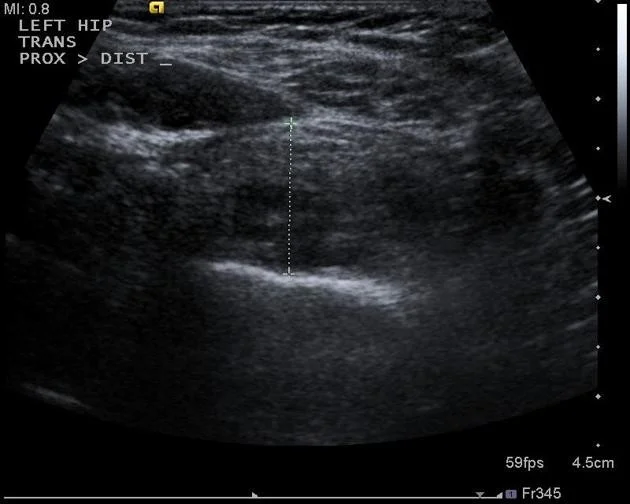

Case 6: 2-year-old with Fever, Vomiting, Pain L Hip

Patient Profile: 2-year-old with fever, vomiting, pain L hip, limited ROM

Key Features:

- Localized osteopenic lesion upper metaphysis L femur

- Reaching epiphyseal plate

Differential Diagnosis: Osteomyelitis, Septic arthritis

Further Investigation:

- CBC, Diff. WBC, CRP, ESR

- Ultrasound

- MRI

Ultrasound Findings: U/S: large hip effusion with echogenic content (Pus)

MRI Findings: MRI: hyperintense T2, Oedema, Fluid collection outside bone, Effusion in hip joint